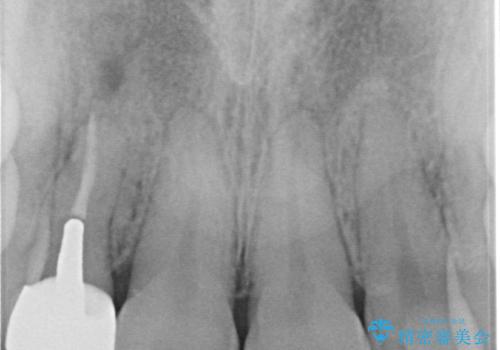

被せ物と歯の境の位置が歯肉の上に設定されており、それによって審美障害が起きていました。

歯と被せ物の境を歯肉縁下0.5㎜に設定して形成を行いオールセラミッククラウン(スペシャル)で治療を行いました。